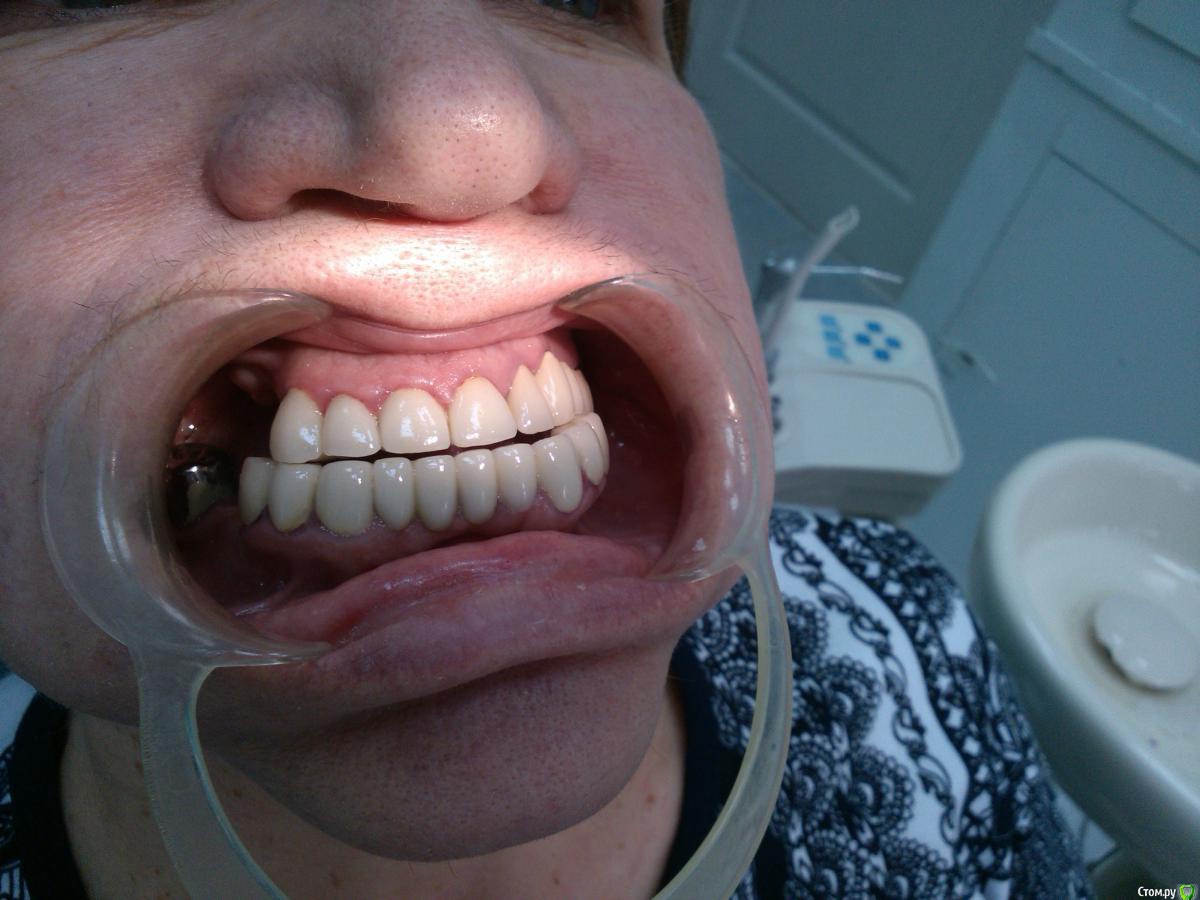

Невероятный Алк2 Опубликовано 31 марта, 2015 Поделиться Опубликовано 31 марта, 2015 Помогите спланировать план лечения. Пациентка протезировалась больше года назад в другом городе. Была у меня на консультации где то пол года назад, на тот момент были жалобы на то что зубы не смыкаются (фото тогда не делал). при осмотре была небольшая прогения и небольшая шель в области зубов 2.3 2.4 и 3.3 3.4. подкорректировал немного по прикусу по прикуссу и отпустил. вот она появилась снова утверждая что нижние зубы выдвигаются вперед. при осмотре то что на фото (за качество извините фоткал на телефон). пациентка хочет все переделать чтобы было красиво. у меня затруднения с выбором конструкции. если кто то что то посоветует, буду очень признателен. заранее спасибо. Ссылка на комментарий

Невероятный Алк2 Опубликовано 1 апреля, 2015 Автор Поделиться Опубликовано 1 апреля, 2015 Какого возраста девушка? Есть ли финансовые ограничения? Готова ли на полную переделку всего рта? Есть ли возможность имплантации или рассматривается только старое традиционное лечение? Есть хороший ортодонт рядом?1. Пациентка 54 года рождения.2. Вариант скорее больше бюджетный.3. По поводу переделки всего, от пациентки поступило предложение удалить весь низ и сделать полный съемный. Посоветовал ей не рубить с плеча.4. По поводу имплантации не разговаривали, но скорее нет чем да из финансовых соображений.5. Ортодонта не плохого найти можно если потребуется. Ссылка на комментарий

Doc Опубликовано 1 апреля, 2015 Поделиться Опубликовано 1 апреля, 2015 Понятно. Тогда для начала надо бы понять откуда такая прогения. По снимку не понять, то ли челюсть выдвинула, то ли запротезировали неправильно, то ли по жизни такая. Потому начать с определения правильного положения, сделать времянки или капу, перепрограммировать, потом протезировать. Внизу удалять все я бы не стал. Полный съемный это не подарок, тем более зубов хватает. Семерку да, пора вроде убрать, там бифуркации нет, а остальные под коронки и бюгель, либо просто съемный. Вверху та же история - смотреть что живет, что нет, потом коронки и съемный или бюгельный, в зависимости от финансовых возможностей пациентки. Из бюджетного без имплантации тут особо ничего не придумаешь. Ссылка на комментарий

Невероятный Алк2 Опубликовано 1 апреля, 2015 Автор Поделиться Опубликовано 1 апреля, 2015 Ну челюсть точно не выдвинула, это положение в центральной окклюзии. Doc, извинити если вдруг спрошу глупость, но что вы имеет в виду говоря перепрограммировать? Ссылка на комментарий

Невероятный Алк2 Опубликовано 1 апреля, 2015 Автор Поделиться Опубликовано 1 апреля, 2015 А если с помощью ортодонта вернуть нижние зубы на место? Просто визуально определяется сильный ноклон нижних зубов вестибулярно. Видимо доктор который протезировал пытался вывести параллели путем сильной обработки с вестибулярной поверхности. Ссылка на комментарий

Doc Опубликовано 1 апреля, 2015 Поделиться Опубликовано 1 апреля, 2015 А если с помощью ортодонта вернуть нижние зубы на место? Просто визуально определяется сильный ноклон нижних зубов вестибулярно. Видимо доктор который протезировал пытался вывести параллели путем сильной обработки с вестибулярной поверхности.Если "девушко" 1954 года рождения, с проблемами в финансовом плане, то вряд ли она на это пойдет. Кроме того, там зацепиться особо не за что, чтобы эти зубы тянуть, только если импланты поставить для анкоража. Ну а импланты это опять другой уровень цен. Ссылка на комментарий